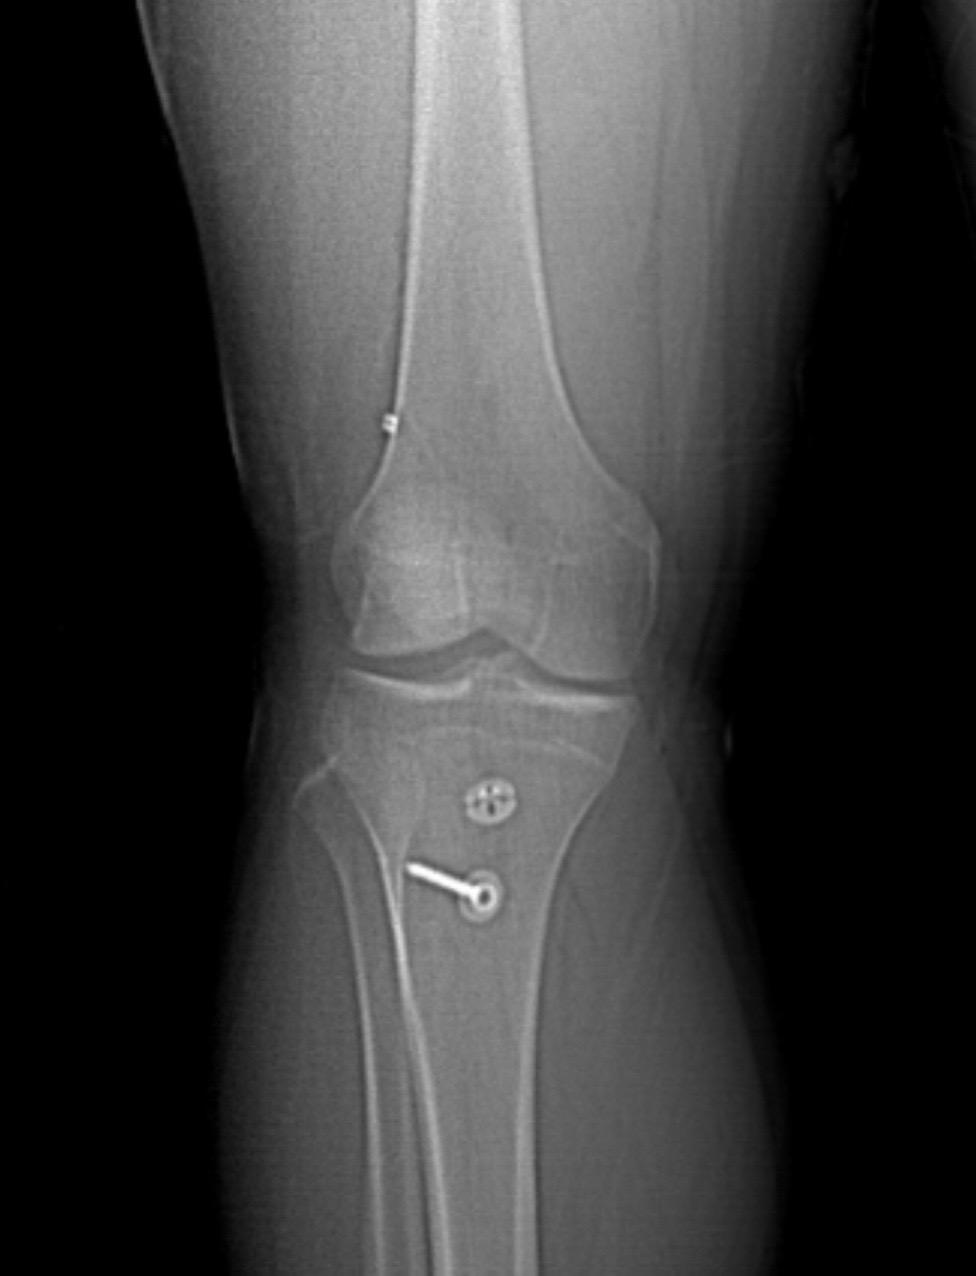

前交叉韧带重建。前叉重建+半月板修复,祝他早日康复!